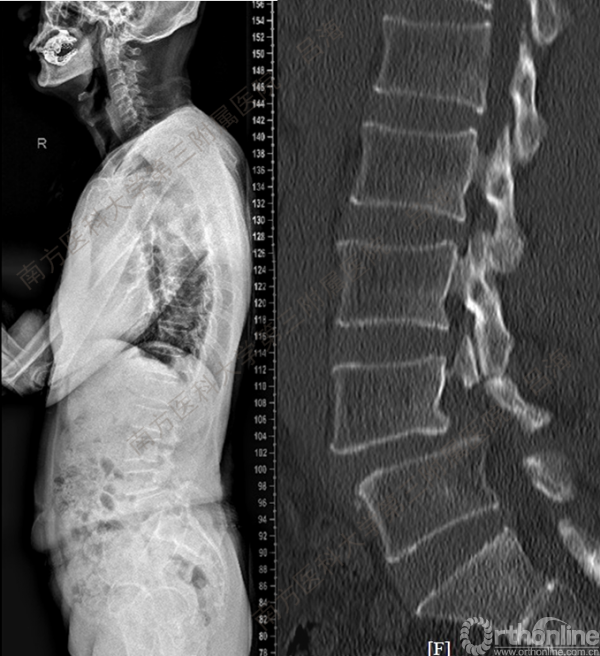

随着社会老龄化进程加快,胸腰椎退行性病变的治疗已经成为脊柱学术界的一个热点话题。MIS-TLIF手术可以治疗多种不同的胸腰椎退行性疾病,南方医科大学第三附属医院吕海教授结合病例为我们一一展示了该术式在治疗不同胸腰椎疾病时的具体手术过程。